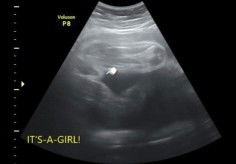

Kira kira cowo apa cewe yaa

Bunnn. Ini kira kira cewek apa cowok yaa. Kata dokter nya cewek, tapi kok kek ada monas nya wkwk.

Tapi itu kek ada Monas nya bun